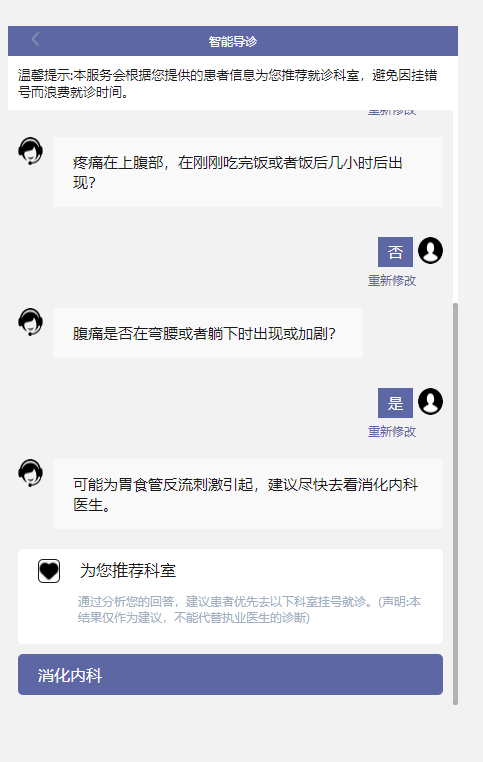

1、通过点击部位选项,选择自己身体不适的部位,系统会列出该部位的所有症状疾病,患者只需要选择与自己相同的症状,如某些疾病还有需要再确定的地方,患者再次选择相对应的选项,通过智慧导诊系统多维度计算,根据情况提供相关建议,最终推荐就诊的科室。